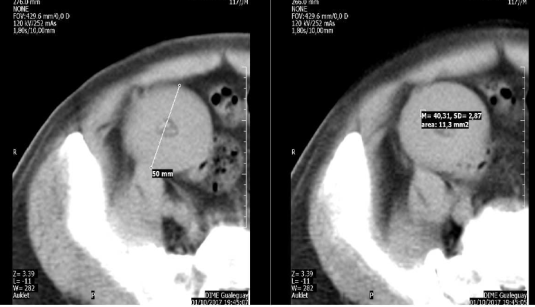

mejoría parcial del cuadro. Se efectuó una tomografía computada de abdomen, que

mostró una masa ovoidea en la fosa ilíaca derecha de 6 x 5 x 4 centímetros. La misma

se encontraba en profundidad, separada del músculo recto anterior y del

transverso por un delgado plano de tejido graso que mostraba muy discretos

cambios densitométricos. En sentido céfalocaudal, alcanzaba el polo renal inferior y la vejiga,

respectivamente, sin tener aparente relación con ellos. La lesión era bien

definida, de contornos netos y densitometría de tejido blando, con un pequeño

núcleo de densidad grasa, que a su vez, contenía una pequeña calcificación. No había

clara relación con el tubo digestivo; tampoco

presentaba colecciones, adenomegalias, ni cambios inflamatorios

relacionados (Figura 1).

Figura

1. Corte

tomográfico horizontal del abdomen que muestra la

tumoración redondeada.